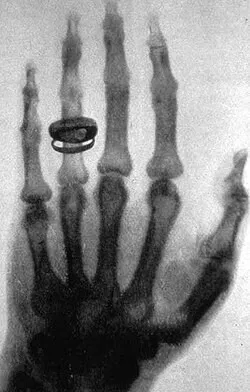

- τι προσφέρει αυτό που γιορτάζουμε; Η Ακτινολογία είναι μια από τις πιο καίριες ειδικότητες της Ιατρικής που τα τελευταία χρόνια, λόγω της εξέλιξης της τεχνολογίας που τη συνοδεύει, έχει αποκτήσει ανεκτίμητη αξία και αποτελεί ουσιαστικό συνδετικό κρίκο στη διάγνωση και διαχείριση των ασθενών. Συνοδεύεται και ενισχύεται από πληθώρα τεχνολογικών εξελίξεων, που είναι εντυπωσιακές αν θυμηθούμε την εποχή που ο κύριος Röntgen απεικόνισε την παλάμη της συζύγου του, με τη βοήθεια των «αόρατων» ακτίνων Χ, 130 χρόνια πριν στις 8/11/1895. Όλα αυτά τα χρόνια, έχουν σημειωθεί άλματα στη δυνατότητα της απεικόνισης πολλαπλών σημείων και συστημάτων του οργανισμού, σε όλες τις ηλικίες με λεπτομέρειες που συχνά θυμίζουν ανατομικό ή χειρουργικό παρασκεύασμα. Με αυτόν τον τρόπο, η Ακτινολογία έχει βοηθήσει στη διάγνωση πολλαπλών παθήσεων, συχνά σε πρώιμο στάδιο και έχει συνεισφέρει ουσιαστικά στην αποτελεσματικότερη θεραπεία και παρακολούθηση πολλαπλών ασθενειών, δίνοντας ώθηση στην πρόοδο και την εξέλιξη της Ιατρικής.